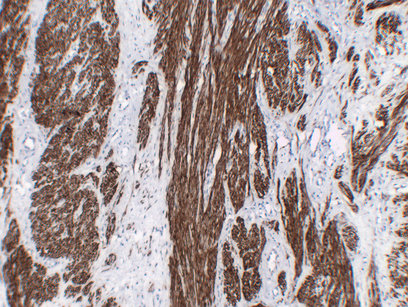

ARG66482 anti-Calponin 1 antibody IHC-P image

Immunohistochemistry: Paraffin-embedded Human leiomyoma stained with ARG66482 anti-Calponin 1 antibody at 1:200 (4°C, overnight). Antigen Retrieval: Citric acid buffer (pH 6.0) was used.